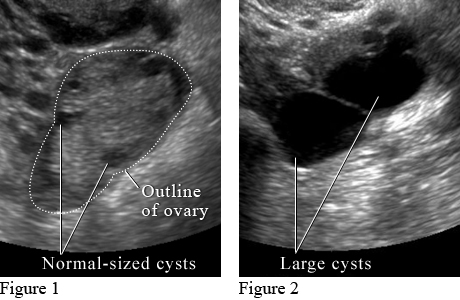

Figure 1 shows small normal-sized cysts. Figure 2 shows large cysts that affect the ovary and may cause pain.